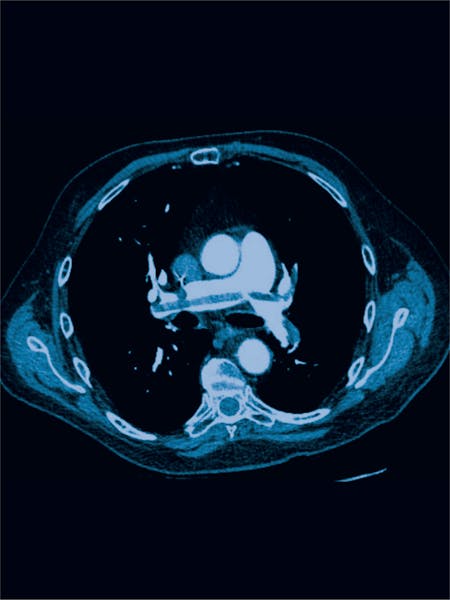

Teste imagistice utilizate pentru confirmarea diagnosticului includ:

- CT-ul toracic: Un tomograf computerizat poate identifica cheagurile de sânge în arterele pulmonare.